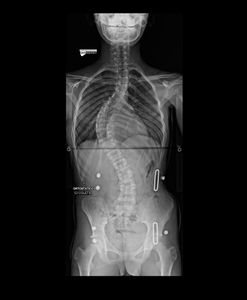

Há um ano, sua mãe reparou que ele começou a andar torto e comentou a situação comigo, Adriana, com quem ela trabalha ocasionalmente. Ofereci de levarmos o menino a um ortopedista particular e assim foi. Na consulta, o médico realizou exames de imagem (anexos a essa campanha) e, chocado, diagnosticou Juan com uma escoliose gravíssima, recomendando cirurgia em caráter de urgência.

De 1 ano para cá, desde o diagnóstico, a angulação da coluna de Juan tem piorado, apesar do uso do colete e do tratamento em sessões de RPG, e a cirurgia é inavitável.

Além da preocupação natural da família com o quadro geral, o grande receio é de que a coluna venha a comprometer o seu pulmão, já que Juan tem asma desde muito novo. Por isso, em razão da urgência e evolução gradativa do quadro, lançamos essa campanha! O valor arrecado será integralmente destinado à cirurgia e ao tratamento da escoliose de Juan.